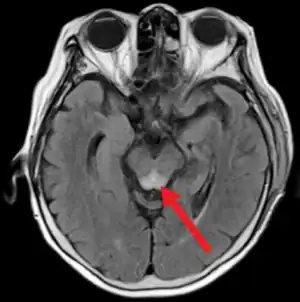

| Wernicke's encephalopathy (type of encephalopathy) | |

- Wernicke's encephalopathy: Arising from thiamine (B1) deficiency, usually in the setting of alcoholism.